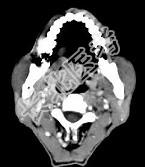

- 多项选择题男性,57岁, 睡觉打鼾,近来加重, CT扫描如图所示,请选择正确的描述和答案  (    )

- A、鼻咽腔偏右侧可见类圆形软组织块影

- B、肿块内密度尚均匀,其上方见较多钙化影

- C、肿块边缘大部清楚,邻近结构未见明显受侵

- D、考虑为鼻咽癌

- E、考虑为鼻咽部多形性腺瘤